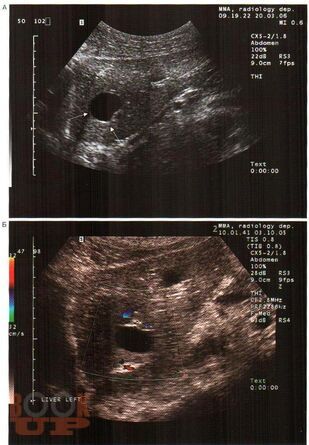

В практическом руководстве отражены вопросы ультразвуковой диагностики доброкачественных, злокачественных опухолей печени, поджелудочной железы, метастатического поражения печени, пороков развития, заболеваний гепатопанкреатодуоденальной зоны. Практическое руководство предназначено для специалистов лучевой диагностики, хирургов, онкохирургов.